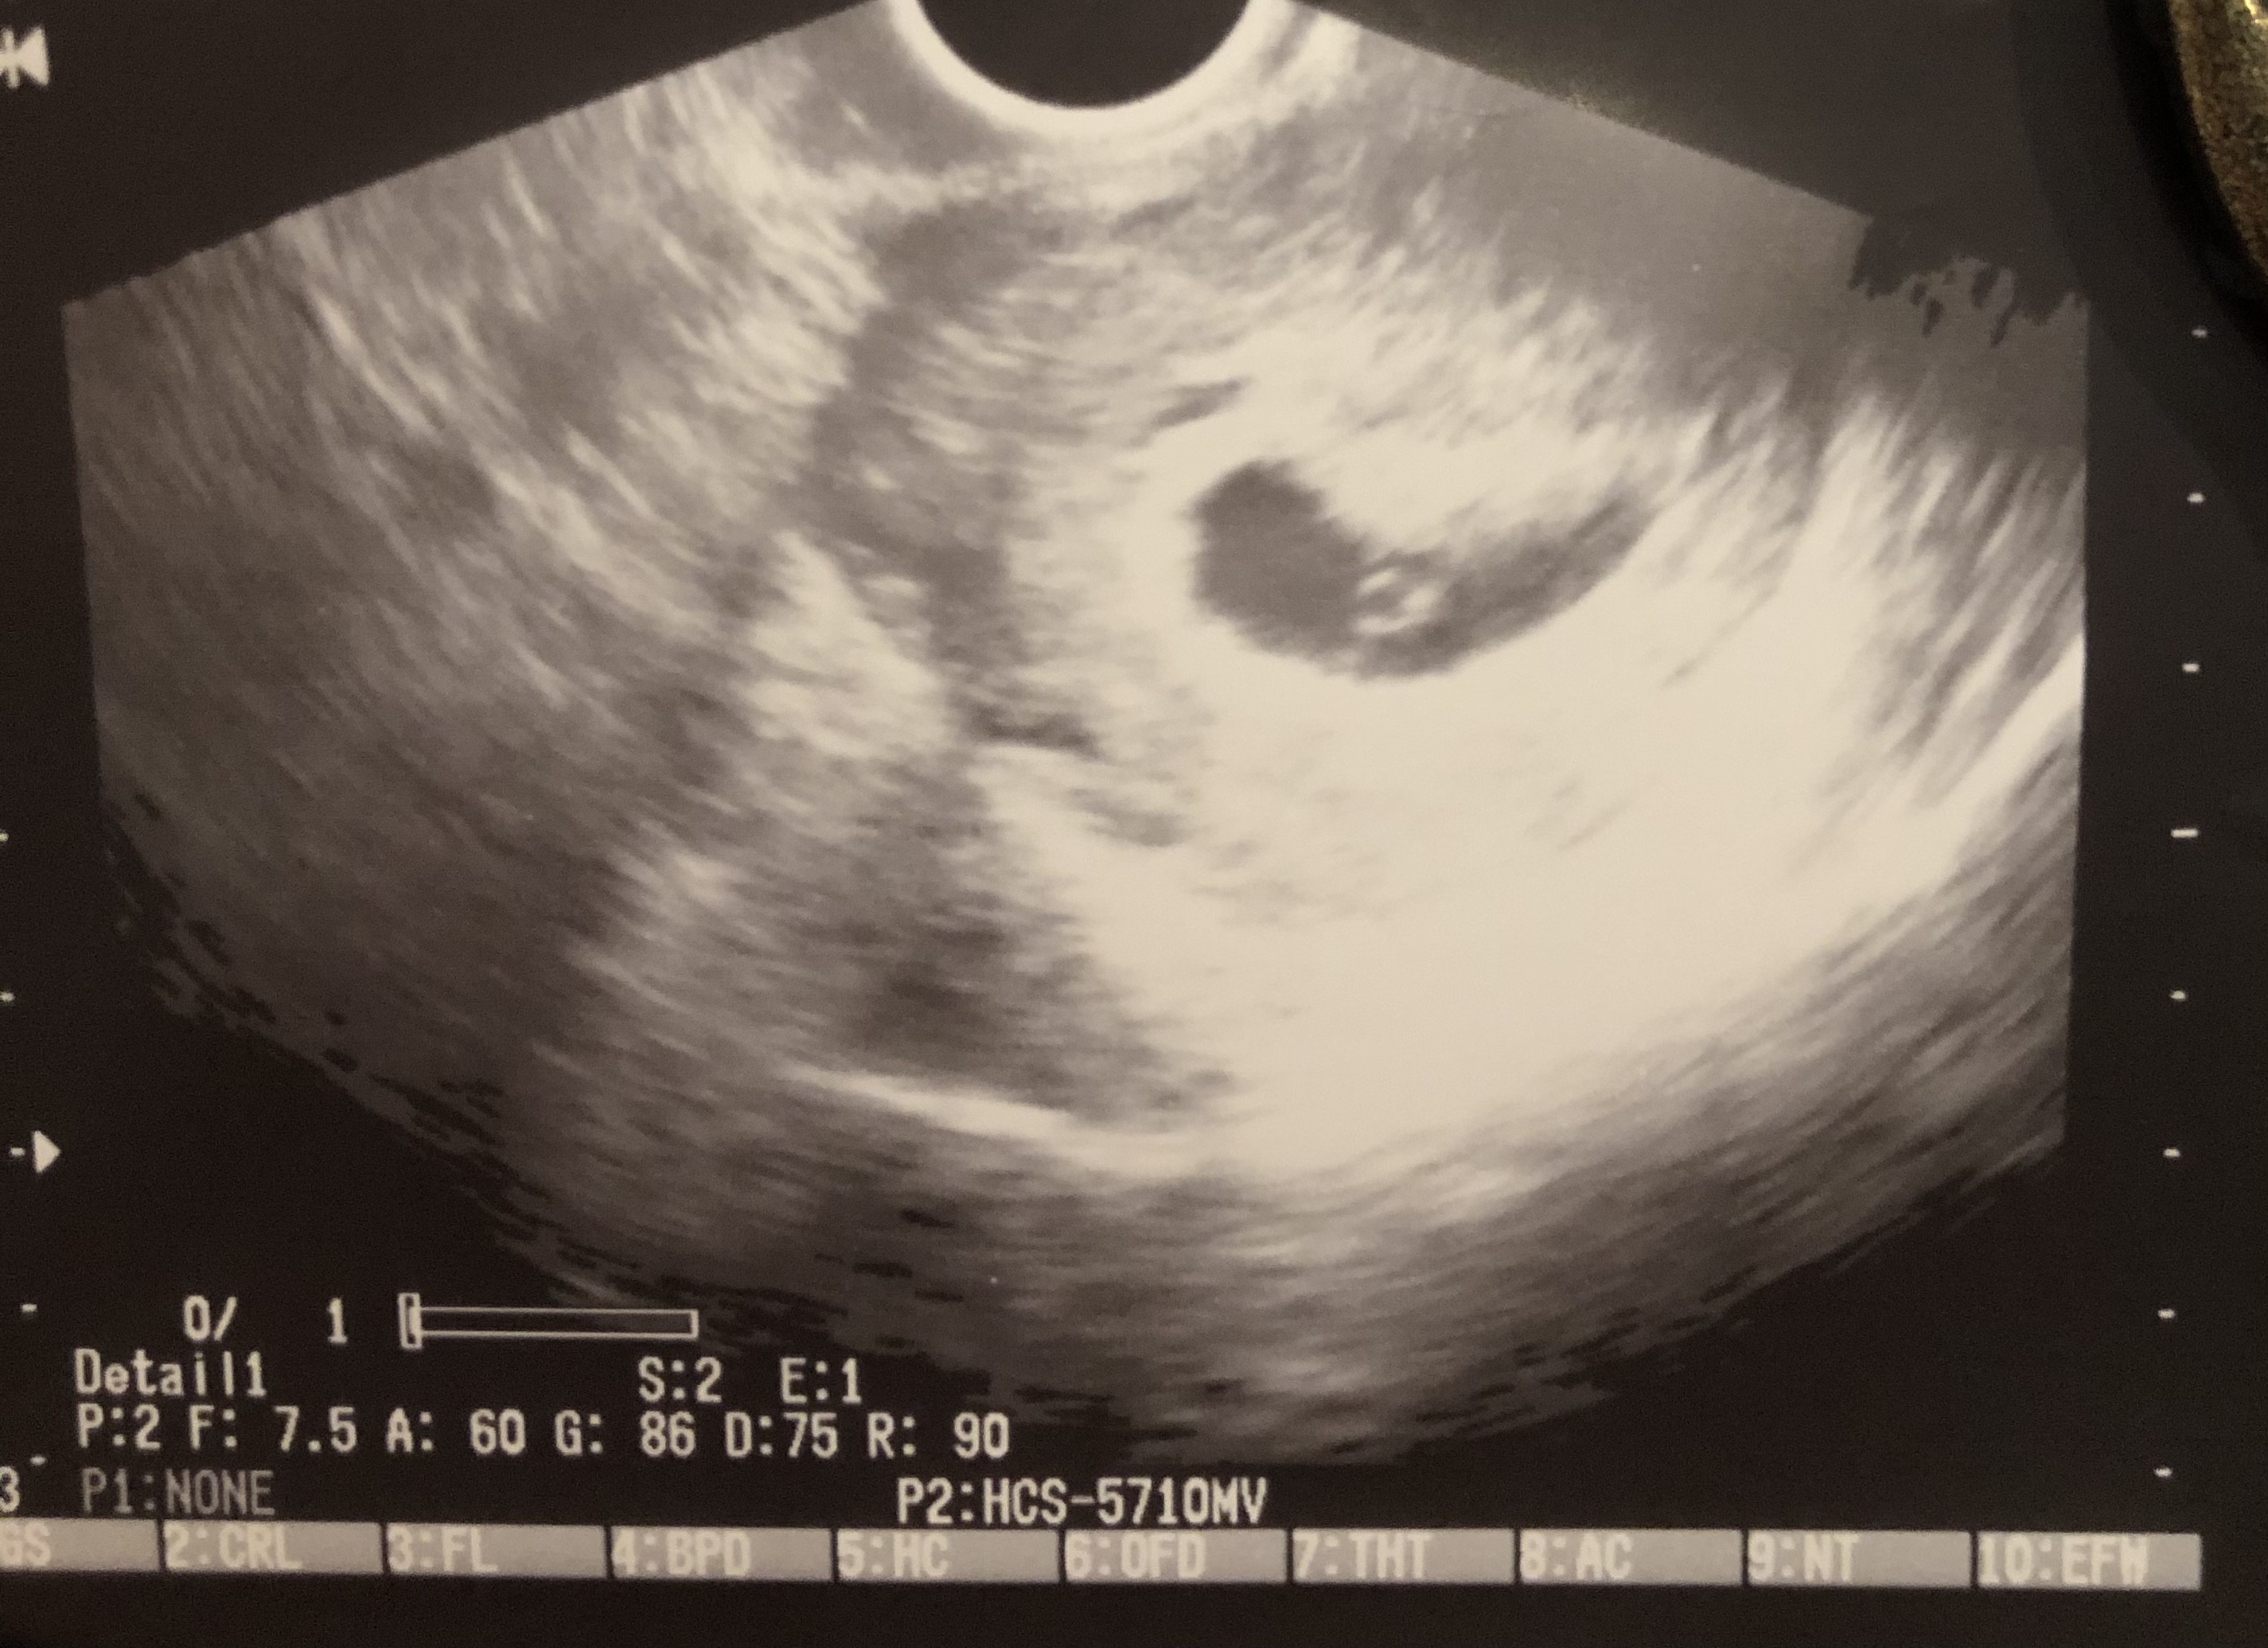

Płaski pęcherzyk ciążowy

Jak w temacie , Drogie Panie. Czy któraś z Was miała z tym ,, problem”- jestem na etapie 6t3d i taki tez obraz otrzymałam od lekarza. Wspomniał, ze być może taka specyfika pęcherzyka. Jak było u Was?